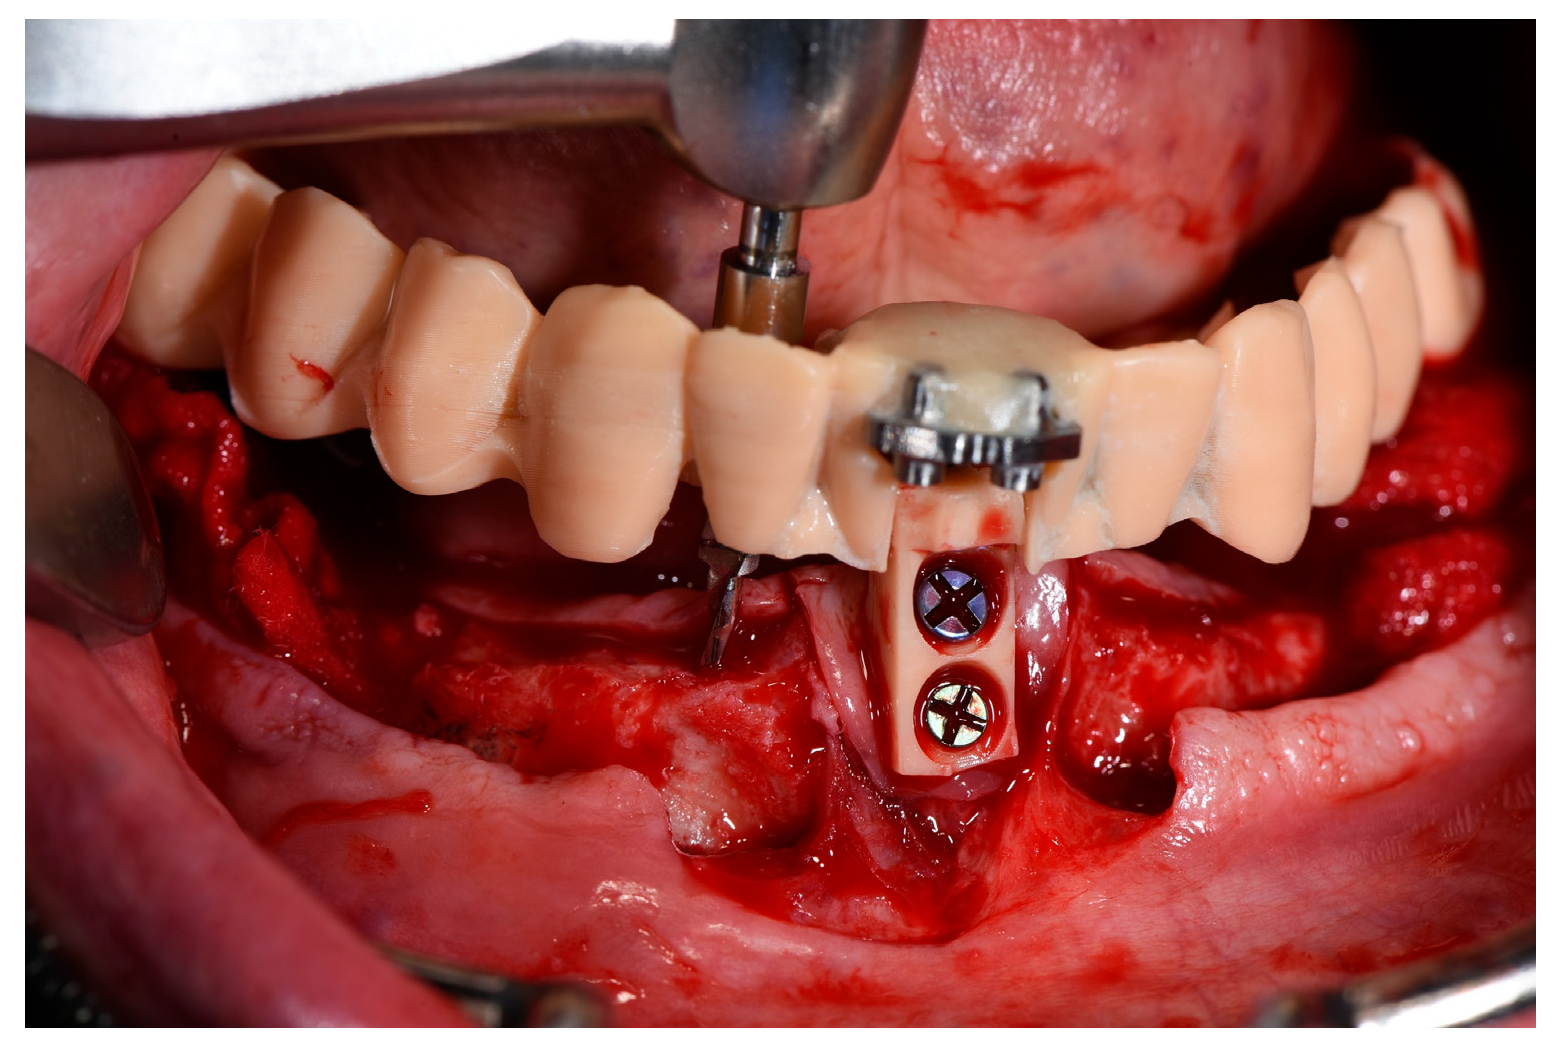

2.2. Impression Reference Technique Device

2.3. Surgical Procedure

2.5. Prosthesis Generation